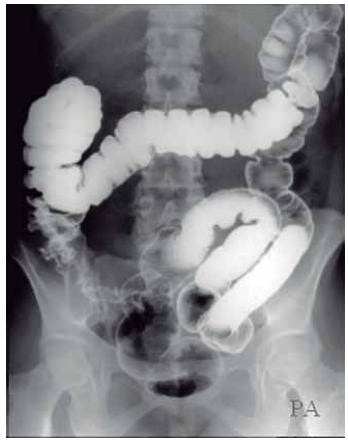

Observe a figura a seguir:

(Arquivo pessoal; imagem usada com autorização)

O duplo contraste no exame contrastado do sistema digestório, enema opaco, contempla a visualização do intestino grosso.

Assinale a alternativa que denomina, corretamente, a sequência da sua divisão.